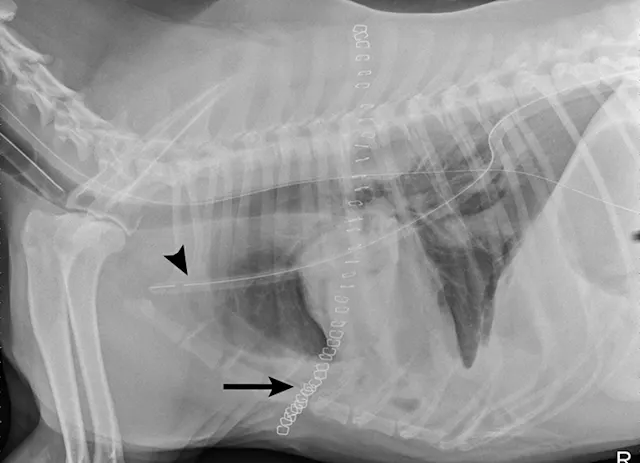

Radiographs obtained after thoracocentesis demonstrated improved pleural effusion and consolidation of the left middle lung lobe (Figure 3). Based on the soft tissue bulge near the hilum and the air bronchocram extending cranially, the primary differential was lung lobe torsion (LLT). Other considerations included pulmonary mass, abscess, or granuloma.

FIGURE 3A

Right lateral (A) and ventrodorsal (B) thoracic radiographs obtained after thoracocentesis showing improvement in pleural effusion with a persistent soft tissue opacity in the left mid-to-cranial thorax. An air bronchogram is seen extending cranially from the hilus (arrowhead) where a subtle bulge (arrow) is present.